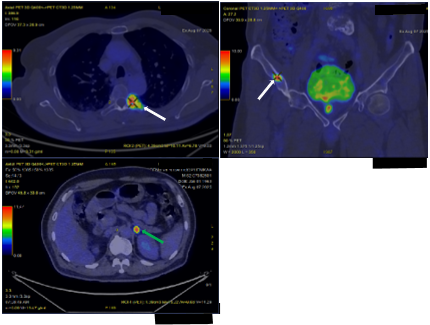

Sau đó, bệnh nhân được chụp PET/CT toàn thân, một phương pháp y học hạt nhân hiện đại, rất có giá trị trong phát hiện các tổn thương, đặc b iệt là các tổn thương di căn hạch và di căn xa. Phim chụp cho thấy bệnh nhân có rất nhiều tổn thương tại nhu mô phổi hai bên, tại tuyến thượng thận trái, tại xương nhiều vị trí và tại tuyến tiền liệt, tăng hấp thu FDG thể hiện tính chất ác tính (Hình 5).

Hình 5: Hình ảnh PET/CT cho thấy: 02 khối u phổi phải, kích thước lớn nhất 16 x 23 mm, xâm lấn vào trung thất (SUVmax: 17,8) và các nốt đặc nhỏ rải rác nhu mô hai phổi, tăng hấp thu FDG (SUV: 10,5) (mũi tên đỏ). Hình ảnh các tổn thương tại xương (mũi tên trắng) tương ứng với các vị trí tổn thương quan sát thấy trên xạ hình xương (SUVmax: 22,2). Hình ảnh nốt tuyến thượng thận trái (mũi tên xanh), tăng hấp thu FDG (SUVmax: 15,2). Hình ảnh tăng hấp thu FDG tại vùng chuyển tiếp,vùng ngoại vi bên phải tuyến tiền liệt và thành dưới bàng quang (SUVmax: 17,1) (mũi tên vàng).